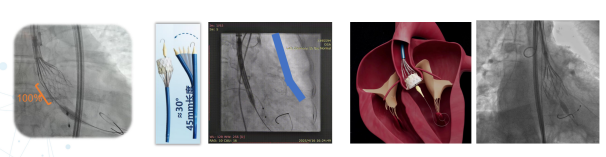

康复大学青岛中心医院林明山教授分享一例“双瓣一站式”高难度VIV病例,深刻展现自膨短瓣在生物瓣衰败VIV中的应用价值。患者83岁男性,于2010年行主动脉瓣置换术、二尖瓣置换术及三尖瓣成形术,现主动脉瓣和二尖瓣生物瓣均出现重度反流,术前超声/CT充分评估后,决定采用经心尖入路,先行主动脉瓣瓣中瓣植入术(TAVR-VIV),顺利送入ScienCrown TAVTA 23mm瓣膜,得益于该款瓣膜短瓣架设计,完全释放后对血流影响小,因此TAVR-VIV术中无需起搏,瓣膜初次释放位置稍浅,部分回收调整瓣膜深度重新释放,即刻造影示瓣膜位置良好,无张力脱钩瓣膜位置稳定,术后TEE示主动脉瓣平均跨瓣压差仅4mmHg。随后行二尖瓣瓣中瓣植入术(TMVR-VIV),经心尖入路植入ScienCrown TAVTF 29mm瓣膜,主动脉根部造影,冠脉显影良好无瓣周漏,术后TEE示二尖瓣平均跨瓣压差仅1mmHg。

TAVR-VIV术后造影

TAVR-VIV术后TEE

双瓣VIV术后最终造影

TMVR-VIV术后TEE